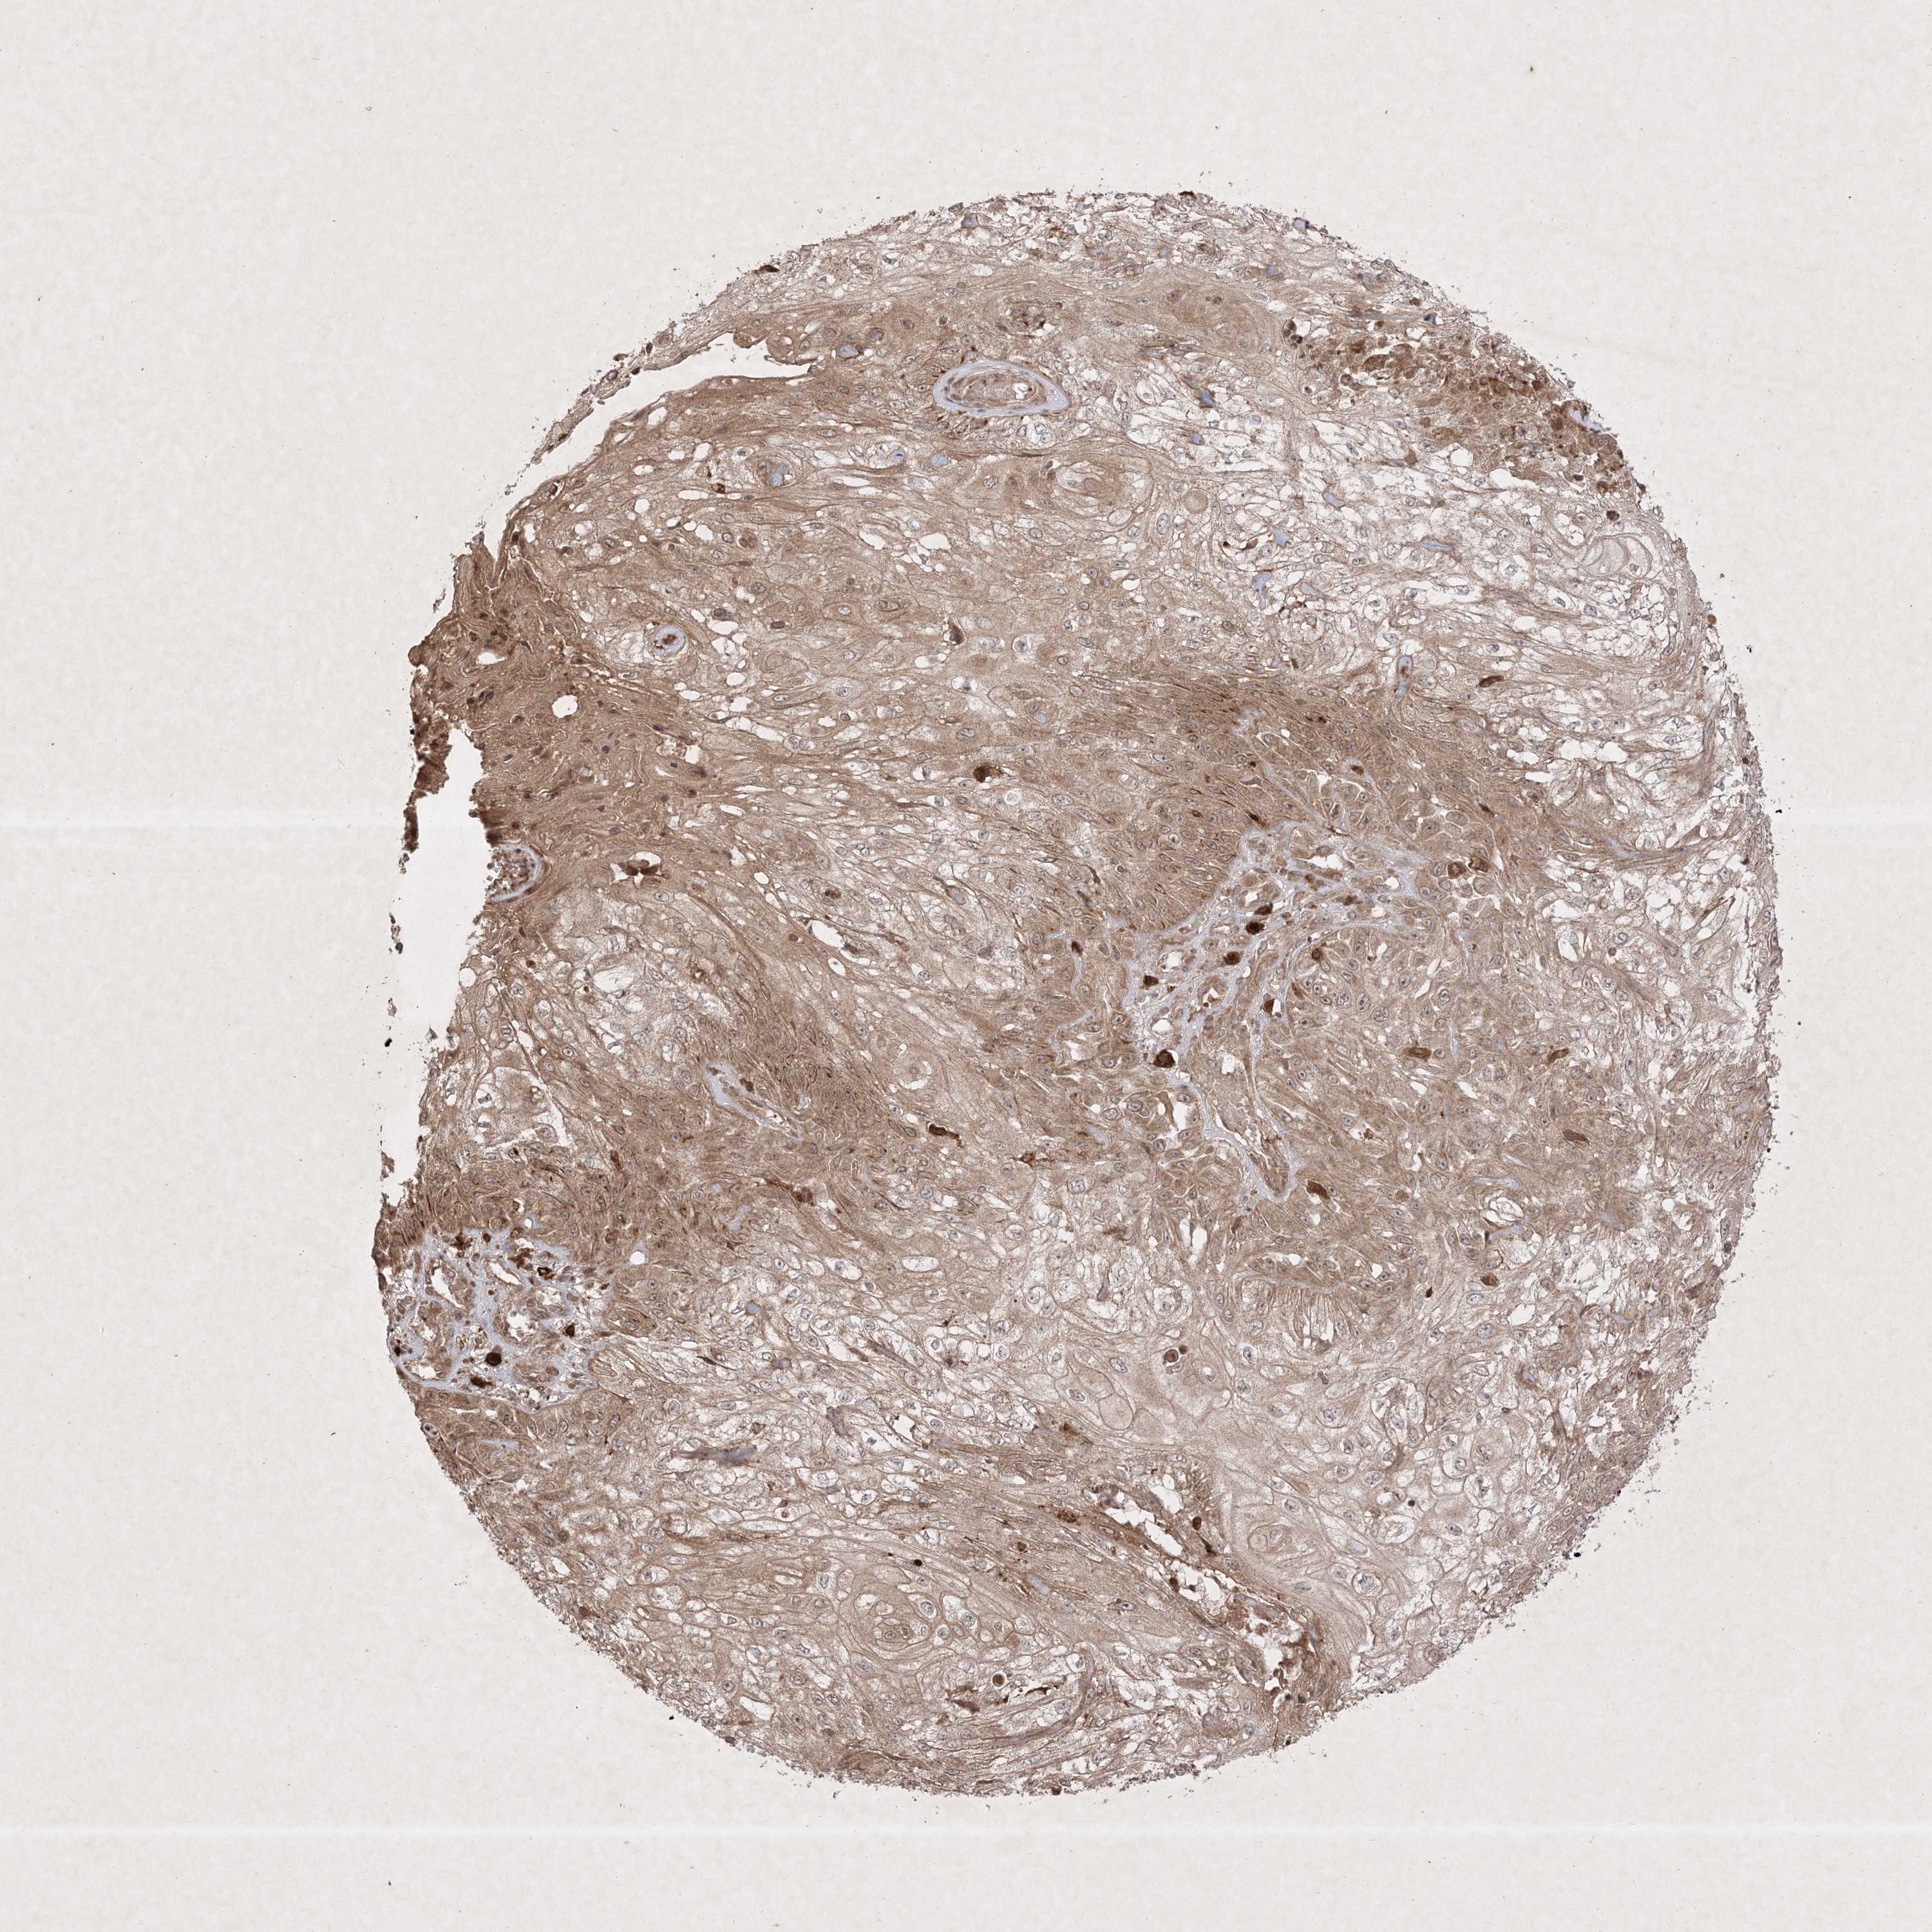

CANCER SKIN CANCER Show tissue menu

Basal cell and squamous cell cancer

SKIN CANCER - Protein expressioni

A mouse-over function shows sample information and annotation data. Click on an image to view it in a full screen mode. Samples can be filtered based on level of antibody staining by selecting one or several of the following categories: high, medium, low and not detected. The assay and annotation is described here.

Each image is clickable and will lead to virtual microscopy that enables deeper exploration of all samples and also displays staining intensity scores, fraction scores and subcellular localization as well as patient and tissue information for each sample.

Antibody CAB032952

Basal cell carcinoma

Squamous cell carcinoma, NOS

Squamous cell carcinoma, metastatic, NOS